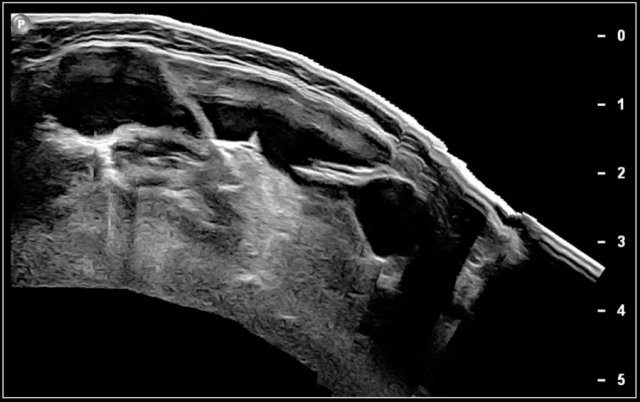

Longitudinal images of the swelling will demonstrate its muscular origin.

Here a video of a two-month-old boy with a torticollis.

A mass is seen within the enlarged sternocleidomastoid muscle.

The diagnosis is fibromatosis collis